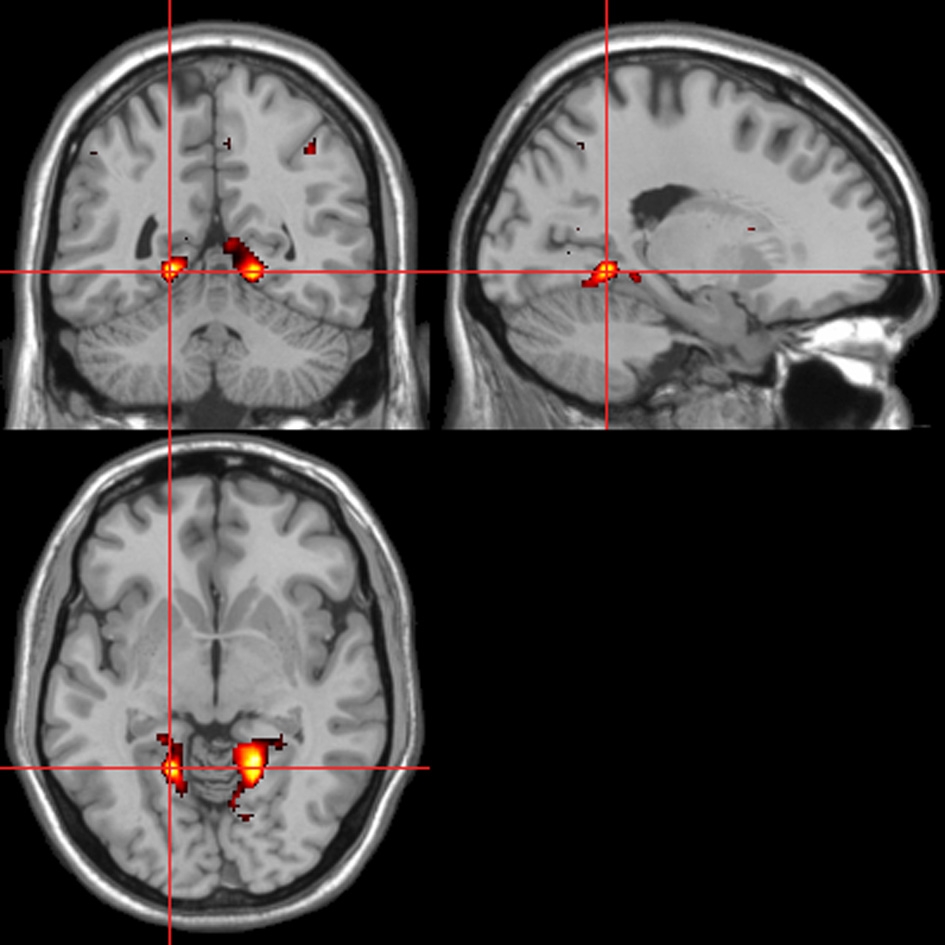

fMRI—autonomic (ISCR)-behavioral response convolved regressor

Across all stimuli, the interaction between autonomic (ISCR) and “threatening” or “harmless” assessment responses—our PAI was associated with activation of right MidFG (BA 10; T&T co-ordinates 24 42 −7) and left mid-cingulate gyrus (BA 24; −6 −23 36). Threatening picture-ISCR interactions were associated with activation of right fusiform gyrus/parahippocampal gyrus (BA 37; Table 3B and Figure 8). Threatening sentence-ISCR interactions were associated with activation of right insula and MidFG (BA 10), left thalamus [ventral posterolateral (VPL) nucleus], left superior temporal gyrus (BA 22) and left cerebellum (Table 4B and Figure 10). Threatening sound-ISCR interactions were associated with activations including left mid-cingulate gyrus, bilateral postcentral gyrus (BA 1/2/3), bilateral IFG (BA 44/47) and right inferior parietal lobule (BA 40; Table 5B and Figure 12). This left mid-cingulate gyrus activation survived FWE correction at p < 0.05.

Figure 8

Pictures. Psycho-autonomic interaction (PAI) between integrated skin conductance response (ISCR) and behavioral response (“threatening” > “harmless”). Flexible factorial design p < 0.001. Extent threshold = 10. See Table 3B anatomical descriptions and co-ordinates.

Figure 9

Sentences. Activations associated with “threatening” compared with “harmless” behavioral responses. Flexible factorial design p < 0.001. Extent threshold = 10. See Table 4A for anatomical descriptions and co-ordinates.